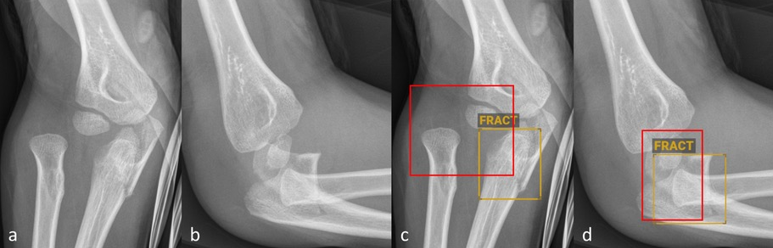

distale metaphysäre Torusfraktur

Abbildung 1: Anteroposteriore (a und c) sowie seitliche (b und d) Röntgenbilder des Vorderarms eines fünfjährigen Kindes ohne (a–b) und mit (cd) Befundmarkierung durch BoneView. Die KI-Software hat die distale metaphysäre Torusfraktur von Radius und Ulna korrekt identifiziert und markiert.

© Altmann-Schneider I, Kellenberger CJ, Pistorius SM, Saladin C, et al. Artificial intelligence-based detection of paediatric appendicular skeletal fractures: performance and limitations for common fracture types and locations. Pediatr Radiol. 2024; 54(1):136-145. http://creativecommons.org/licenses/by/4.0/ Die Abbildung entspricht einem Teil des Originals ohne sonstige Veränderung.

Insgesamt gibt es vergleichsweise wenig publizierte Studien zur Fraktur­diagnostik durch KI bei Kindern und Jugendlichen. Die wenigen durchgeführten externen Validierungsstudien der oben beschriebenen kommerziell erhältlichen Soft­wares zeigen durchweg relativ hohe Sensitivitäten und Spezi­fi­täten (mehrheitlich über 90 %) der jeweils getesteten Softwares [4–6]. Die Studien variieren jedoch stark bezüglich Gesamtanzahl analysierter Röntgen­bilder (zwischen 300 und 2634), Anzahl Röntgenbilder pro Altersgruppe sowie Auswertung der Ergebnisse. Nur eine der Studien schlüsselt die Ergebnisse nach spezifischen Frakturtypen auf, lässt dabei aber die anatomische Lokalisa­tion ausser Acht [6]. In einer am Uni­versitäts-Kinderspital Zürich durchge­führten Studie, haben wir kürzlich in einem Datenset von je 1000 Röntgen­bildern häufiger Fraktur­lokalisationen bei Kindern (Vorderarme, Ellbogen und Unterschenkel) die diagnostische Ge­nau­igkeit der KI-Software BoneView (Gleamer) getestet [7]. Für die Gesamt­heit aller Frakturen wurden ähnlich hohe Sensitivitäten und Spez­ifi­täten wie in früheren Publikationen mit derselben Software gefunden [6]. Abbild­ung 1 zeigt ein Beispiel einer von der KI-Soft­ware korrekt identifizierten Torus­­fraktur des Vorderarms. Die Auf­schlüs­selung nach Frakturtyp hat jedoch deutliche Einschränkungen aufgezeigt. So wurden im Bereich der Vorderarme Bie­gung­s­frakturen nicht verlässlich erkannt. Ausserdem war die Detektionsrate für Avulsionen des Processus styloideus ulnae, Torus­frak­turen des proximalen Radius sowie Olekranonfrakturen im Vergleich zu den übrigen Vorder­arm­frakturen deutlich geringer (< 80 %). Im Bereich der Unterschenkel wurden niedrige Detek­tions­raten für «toddler’s fractures» (74 %) und Tram­po­lin­frak­tu­ren (66 %) gefunden. Bei den Ellbogen wurden nur komplette suprakondyläre Frakturen und Radiushalsfrakturen mit einer Detektionsrate über 80 % erkannt. Die Detektion von Gelenkergüssen im Ell­bogen als indirektes Frakturzeichen war nur moderat. Luxationen im Ell­bo­gengelenk wurden nicht verlässlich erkannt (Abbildung 2). Zusammen­fassend lässt sich also festhalten, dass gerade die – zum Teil diskreten, jedoch äusserst relevanten – Befunde, die dem etwas weniger geübten Auge entgehen könnten, auch von der Software nicht verlässlich erkannt werden.